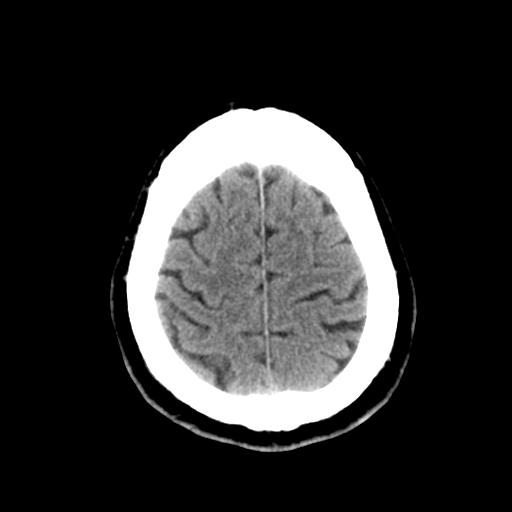

标题: CT28335:男,58岁,请各位看看是不是有脑积水,蝶窦内高密 [打印本页]

标题: CT28335:男,58岁,请各位看看是不是有脑积水,蝶窦内高密

轻度积水,蝶窦正常。

脑积水!建议行mri!

1)脑积水。2)副鼻窦炎。